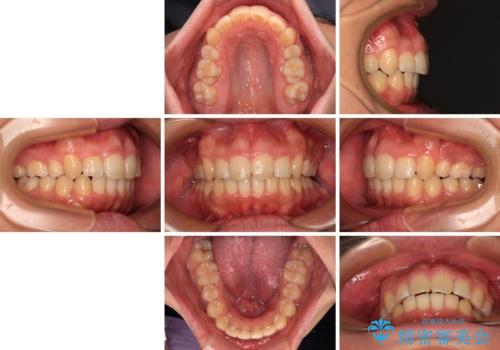

【モニター】後戻りで飛び出してきた前歯 ワイヤー装置での再矯正

- 学生時代に抜歯矯正した歯列が後戻りしてきたとのことで来院された患者様です。

舌の突出癖が原因で上顎前歯が前方に移動したと考えられたため、舌のトレーニングを徹底して行っていただきながら、後戻りを解消していくこととしました。

マウスピース矯正でもワイヤー矯正でも対応可能でしたが、患者様の希望によりワイヤー装置による矯正治療を行うこととしました。

ワイヤー矯正ということで、上顎大臼歯を後方に移動するための補助装置を併用して、積極的に前歯を引っ込めていくこととしました。

上顎歯列全体がスムーズに後方移動でき、1年で治療を終えることができました。